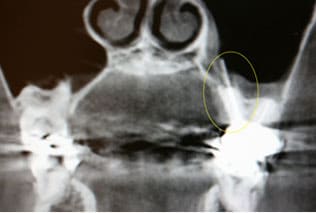

CASE04 歯が原因で起きる副鼻腔炎(歯性上顎洞炎)

鼻の両サイドにある上顎洞という副鼻腔の粘膜が、上顎臼歯部の不適切な根管治療や歯周病などにより炎症を起こし、鼻閉感や頬部痛などを引き起こします。慢性的な炎症ですと、さほど痛みも無く発見が遅れる場合が多く、主に片側で起こります(鼻が原因の副鼻腔炎は両側で発症)。急性症状になると鼻から膿が出たり、激しい痛みを伴いよく耳にする蓄膿症という病気になります。

左側のCTの写真は、不適切な根管治療により(根管に詰める材料が副鼻腔に突き抜けている状態)慢性副鼻腔炎を起こし、片側の強い鼻閉感と左上の第一大臼歯の痛みを主訴にいらした患者様です。根管充填材料の突き抜けている状態と、副鼻空の粘膜の肥厚がCTより確認できました。

慎重に根管の詰め物を撤去し、管から膿抜きをして殺菌消毒をした結果、副鼻腔の粘膜の腫れが消失してきているのが分かります。